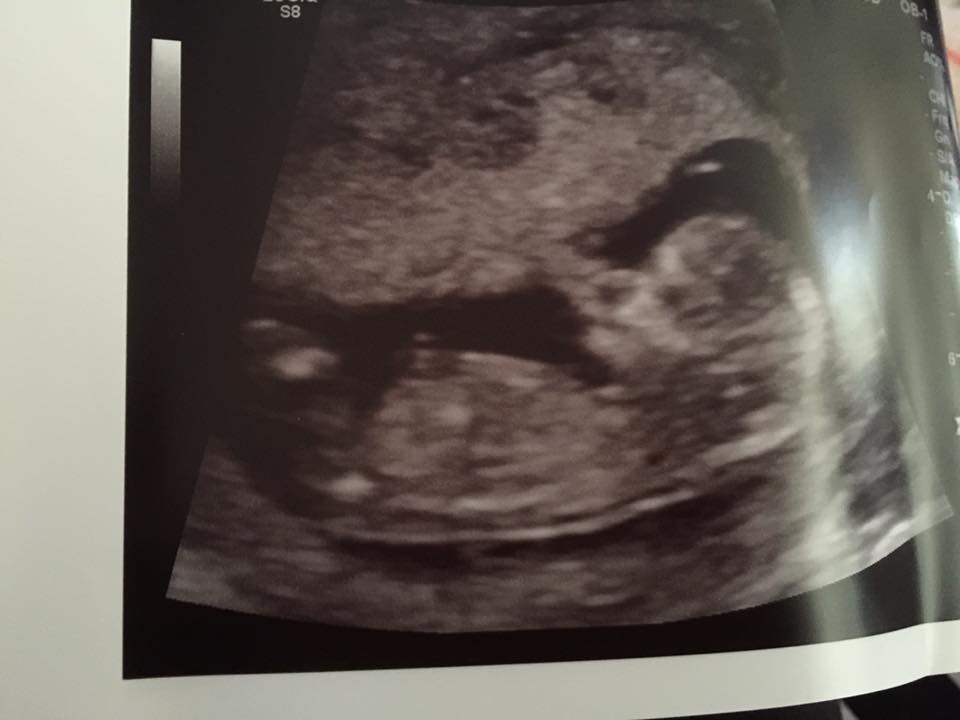

This is the nub of Bub #2

We are thinking its a girl this time because the nub (the first white line is the cord) is very parallel with the spine. Doesn't look risen.

My son and this baby look completely different, my son had a clear risen willy at 12 weeks.

When I saw a potty shot it was round and I saw a couple lines. My son had testicles on his one